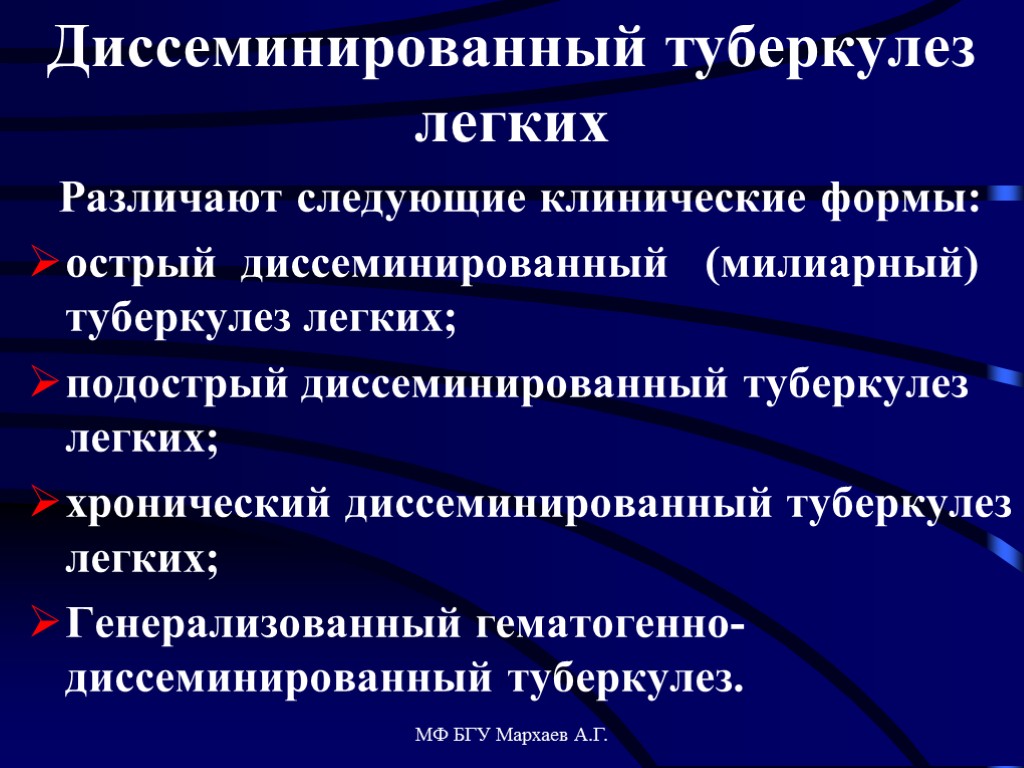

В клинической картине острого гематогенно диссеминированного туберкулеза преобладает